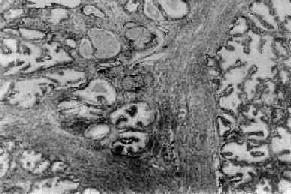

前列腺增生

图14-3 前列腺增生

腺体平滑肌和纤维组织均呈明显增生,有些形成乳头状突入腺泡腔内,有些腔内含有分泌物

镜下,可见前列腺的腺体、平滑肌和纤维结缔组织呈不同程度增生(图14-3)。一般认为前列腺增生是先在尿道两侧的粘膜下,纤维及平滑肌增生,形成多数的小结节状,以后腺体也相继增生,夹杂于增生的平滑肌与纤维组织之间而逐渐形成大小不等的、由纤维及肌组织包绕的腺体结节。增生的腺体腺泡数目增多,体积也呈不同程度扩大。上皮细胞呈柱状或立方形,核位于基底部,也可形成乳头状突入腺泡腔内。腺泡腔内有分泌物及脱落的上皮细胞,偶可见淀粉样小体。纤维及平滑肌细胞肥大、增生,包绕或穿插于增生的腺体之间,形成宽窄不一的间隔。间质中可见多少不等的淋巴细胞浸润。